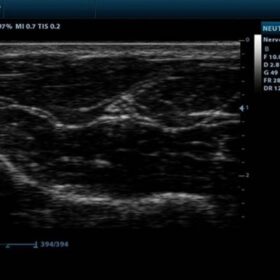

Ultrasound Mindray DP-10 – Image Gallery